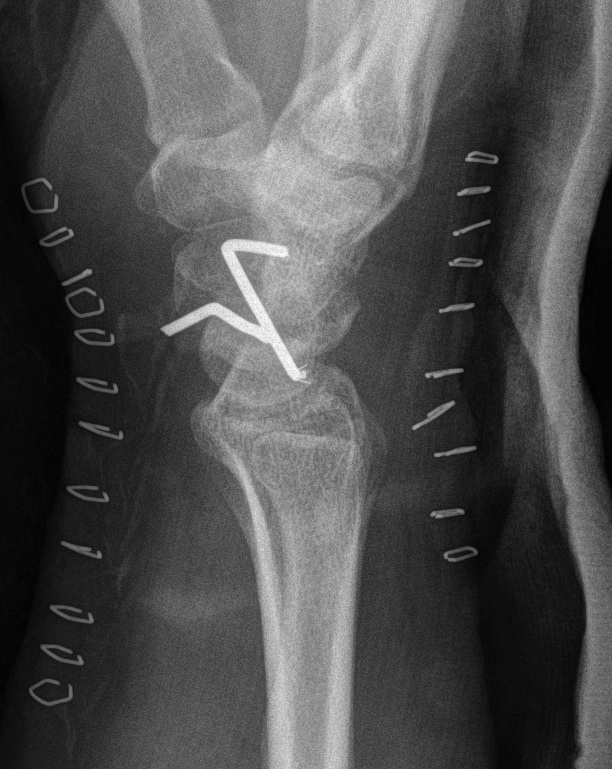

+/- Volar approach

- difficulties reducing lunate

- perform CTD

- repair rent in volar capsule / Space of Poirier

2. Trans Scaphoid Perilunate

Dorsal approach

- ORIF scaphoid fracture

- repair LT ligament

- K wires LT and TC (SL ligament is intact)

- ORIF capitate

- CTD

- repair rent in capsule

Post op

Aim is for a stable but stiff wrist

- 8 weeks in cast, then removal of K wires